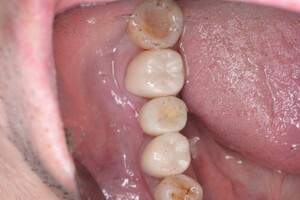

口腔内写真

- Befor

- After

| 年齢 | 50代・男性 |

|---|---|

| 主訴 | 左下7番 |

| 治療内容 | 右下7番インプラント埋入 |

| 治療費 | 合計:572,000円 診断料:55,000円 埋入料:165,000円 サージカルガイド:55,000円 静脈内鎮静麻酔:77,000円 仮歯:55,000円 上部構造(フルジルコニア):165,000円 (2023年1月現在) |

| 治療期間 | 約8ヶ月 |

| リスク・副作用 | リスク・副作用 |

| 治療方針 | 骨が十分にあるため、骨造成をすることなく埋入した。かみ合わせが強いので、負荷がかからないよう、夜寝るときにマウスピースをつけるよう指示をした。 |

| 担当者所見 | 左下6番7番のインプラントは他院で埋入しており、右下7番は抜歯したままで、かみ合わせの歯が落ちてきてしまうのでインプラントを埋入しました。 |